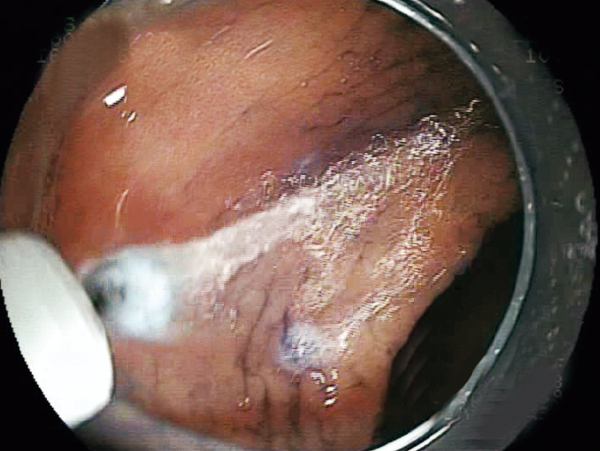

Able to incise the target tissue smoothly from side to side and up to down.

The variation of the tip type and length realizes the optimal approach for each lesion and technique.